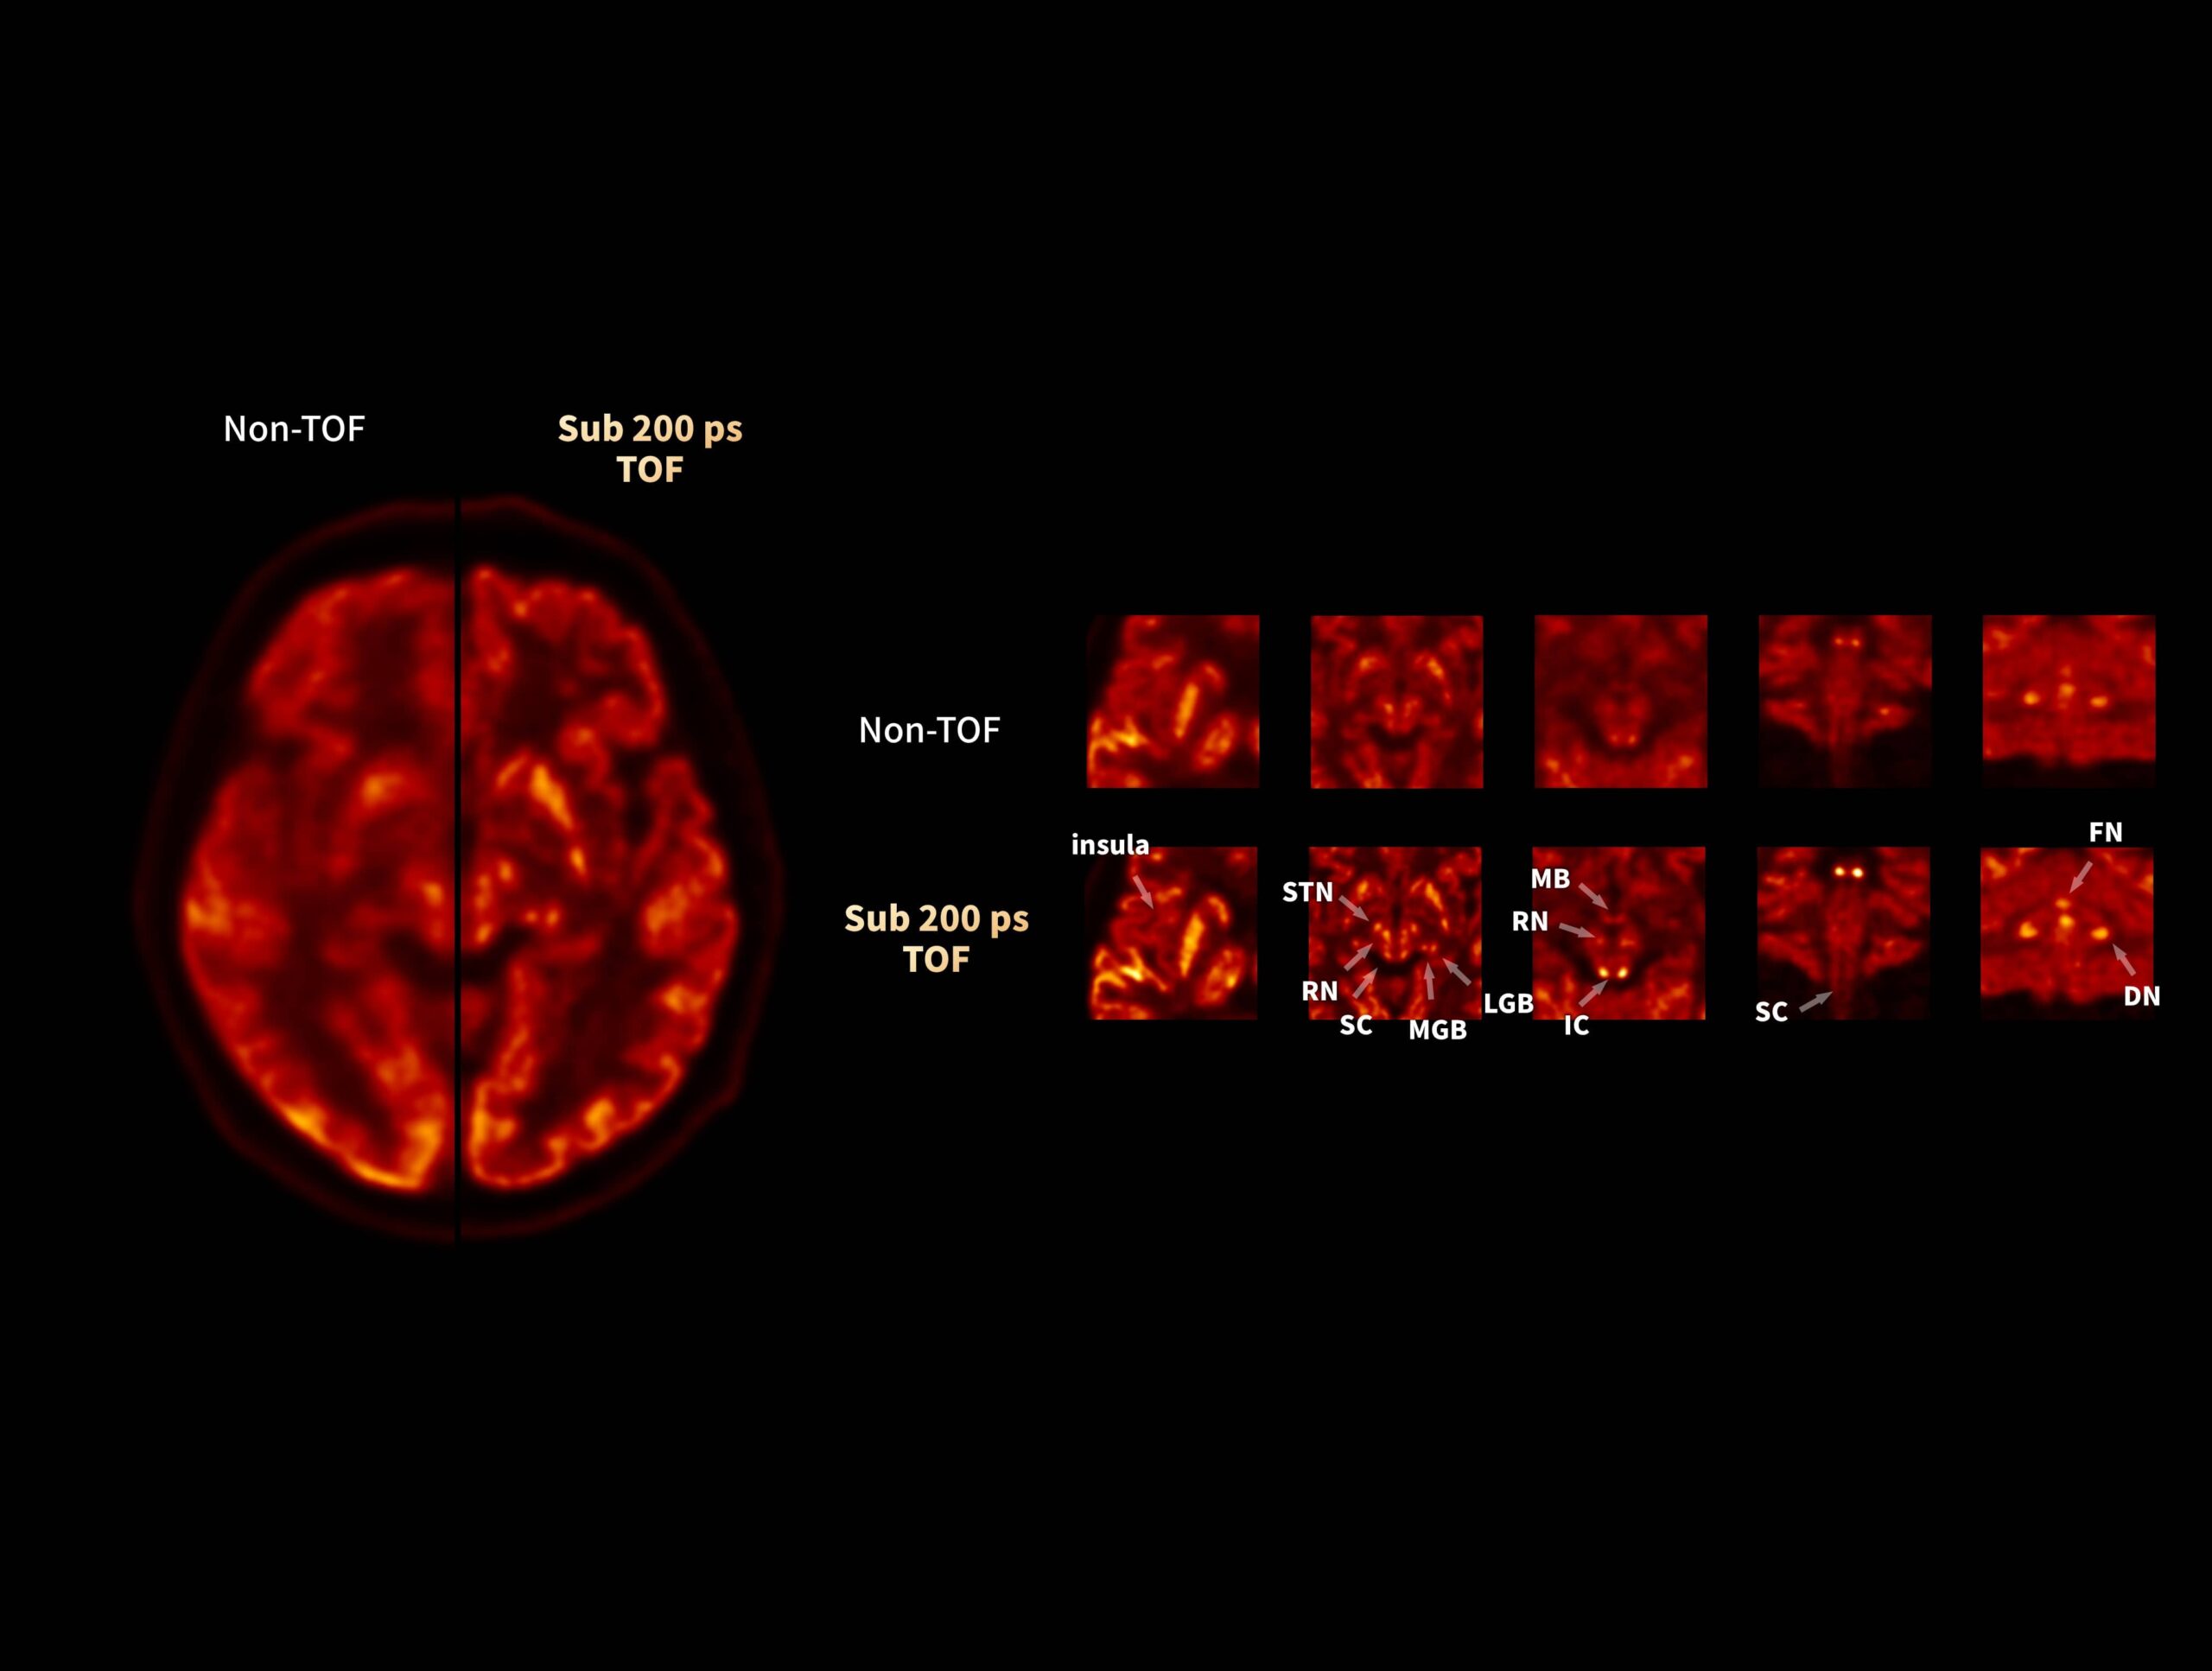

Performanța TOF îmbunătățește imagistica cerebrală PET high-resolution, cu informații anatomice și funcționale combinate